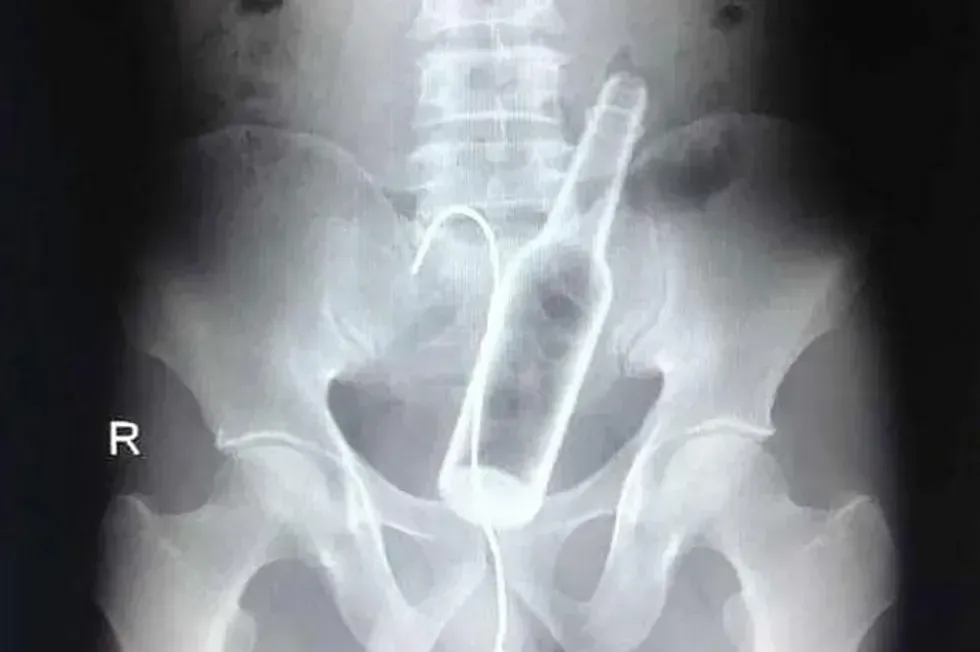

19. A bottle and a hanger